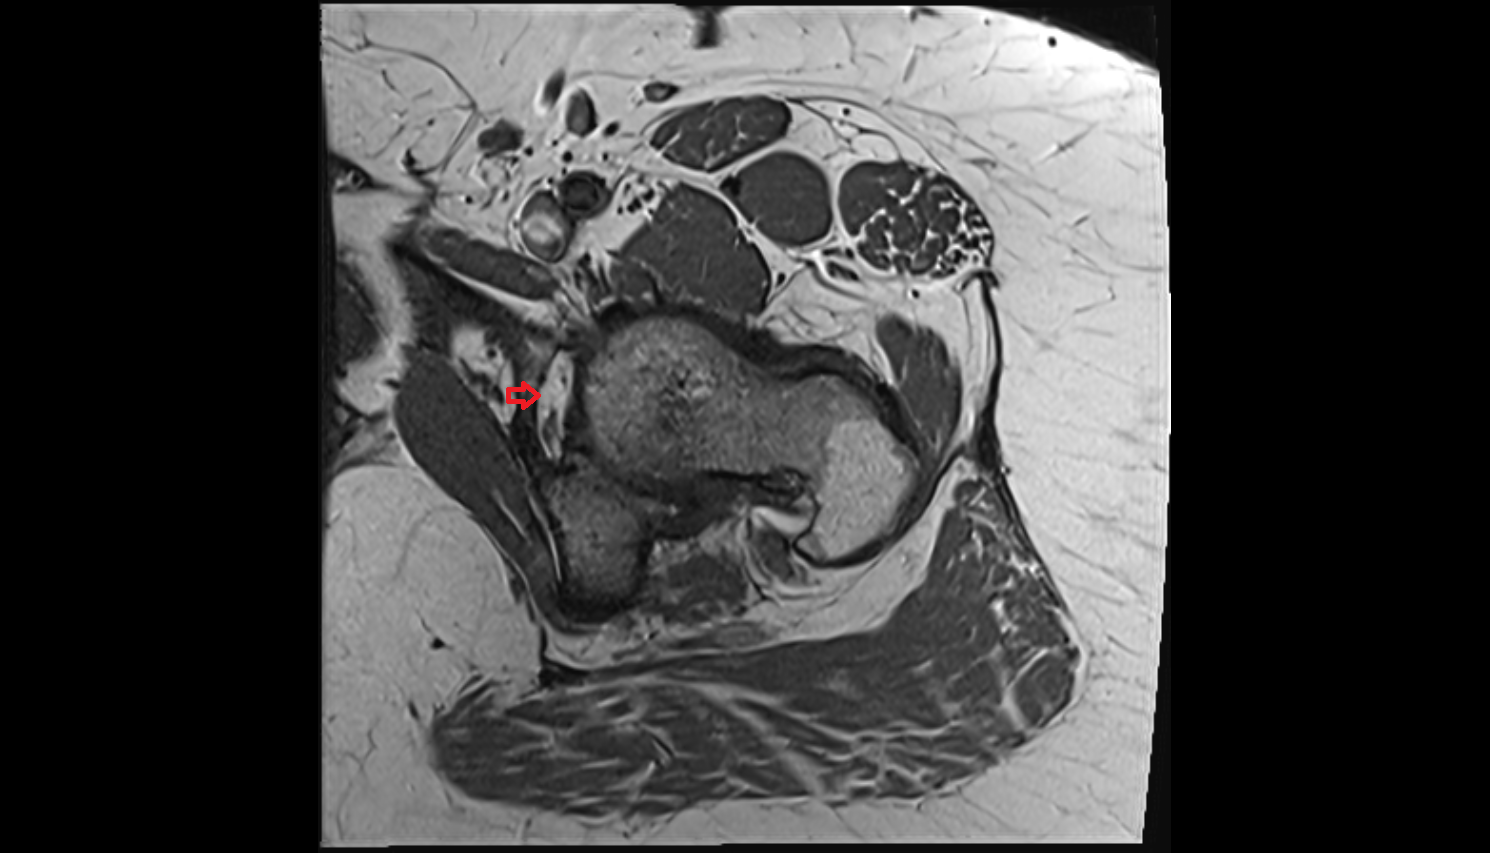

- Uterus

- Body of uterus

- Fundus of uterus

- Cervix of uterus

- Isthmus of uterus

- Vagina

- Fornix of the vagina

- Endometrium of uterus

- Myometrium of uterus

- Perimetrium of uterus

- Junctional zone of uterus